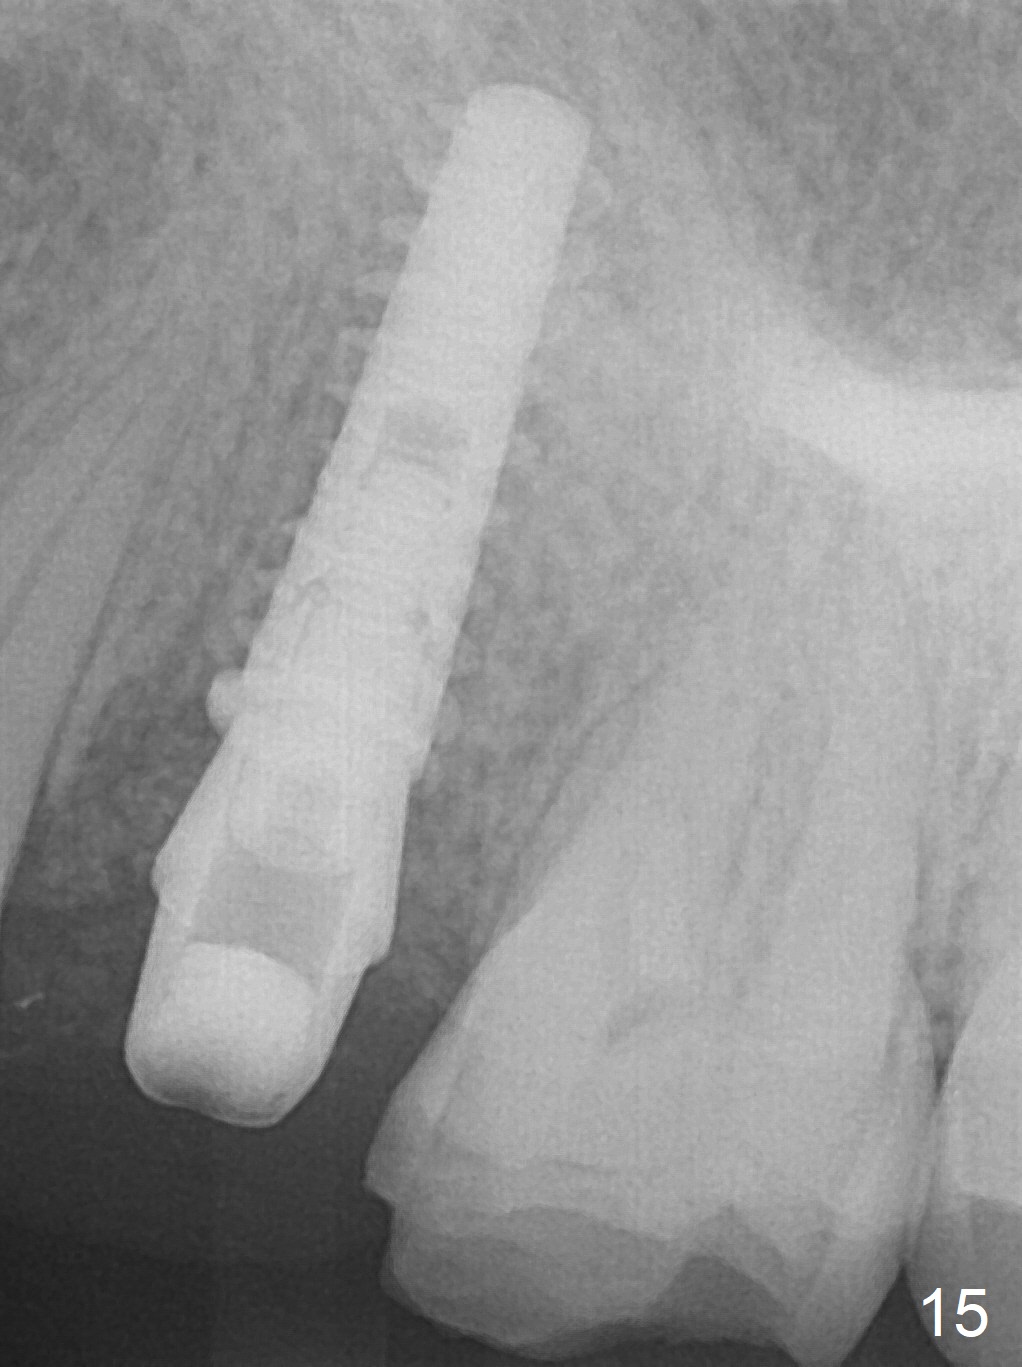

The buccal gingival inflammation subsides 1 week postop (Fig.13,14). There is no bone loss 4 months postop (Fig.15,16). The crown is recemented 6 months post cementation (probably due to short abutment); there is a residual cement (Fig.17 <), which is removed (Fig.18).